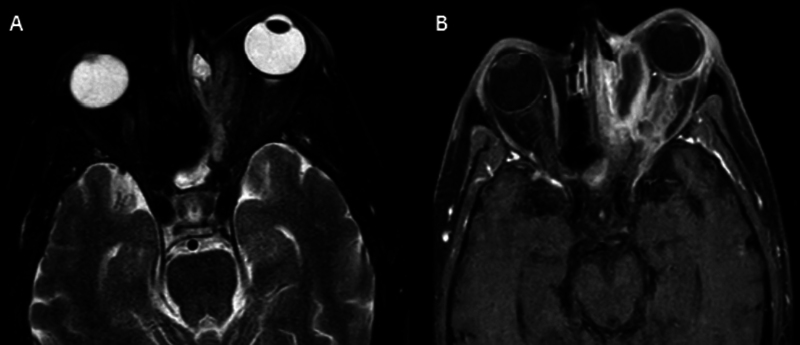

Introduction  Mucormycosis is an aggressive, lethal fungal infection affecting the nasal and paranasal territory in immunocompromised patients. Orbital involvement is not uncommon and may require orbital exenteration. Objectives  The management of orbital involvement in invasive fungal sinusitis is challenging, ranging from conservative retrobulbar amphotericin B injection in the early stages to orbital exenteration in late stages. Endoscopic endonasal debridement is a minimally invasive technique used to manage orbital fungal involvement in the late stages. Methods  Endoscopic endonasal orbital clearance was performed to manage late-stage orbital invasive fungal infection (≥ stage 3c) or after failure of retrobulbar amphotericin B injection with no light perception. Removal of the lamina papyracea (LP) and incision of the periorbita were done to expose all the necrotic intraorbital content in the extra and intraconal spaces. A microdebrider was utilized to debride necrotic fungal infected tissue until a healthy vascularized plane was reached. Gelfoam (Pfizer Inc., New York, NY, United States) soaked in amphotericin B was applied as an adjunctive step to deliver antifungal medication to the orbital content. Results  Fourteen patients were included in the study, 9 of whom were male and 5 female, with a mean age of 58.5 years. Eleven patients showed no evidence of disease progression (complete recovery and cessation of medical treatment). Two patients died 15 days after the surgery. The last patient developed frontal lobe abscess but has been treated with double antifungal medication. Conclusion  Endoscopic endonasal orbital debridement could be an effective method to treat late-stage orbital fungal infection without jeopardizing the patient's life. Level of Evidence : 4.